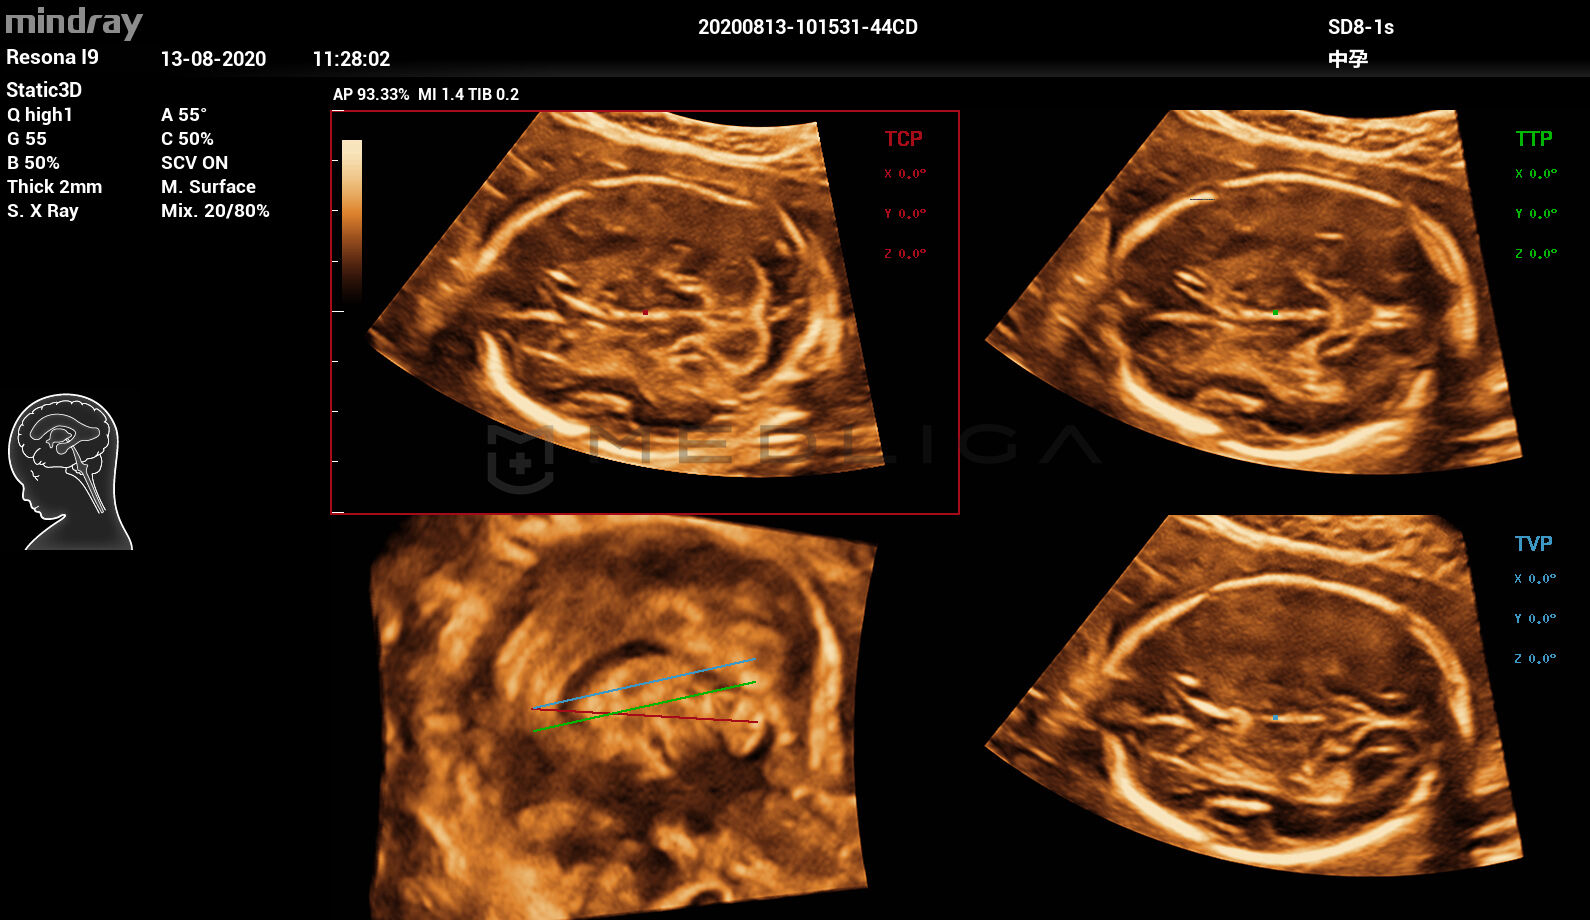

При нажатии на трехмерное изображение мозга плода незамедлительно будут получены

стандартные сканируемые плоскости ЦНС:

- MSP — интеллектуальная медиальная сагиттальная плоскость

- TCP — трансцеребральная плоскость

- TTP — трансталамическая плоскость

- TVP — трансвентрикулярная плоскость

набор соответствующих анатомических измерений:

- BPD — обмер и вычисление бипариентального размера головы

- HC — окружность головы

- OFD — лобно-затылочный размер головы

- TCD — межполушарный размер мозжечка

- CM — ширина большой цистерны

- LVW — ширина боковых желудочков